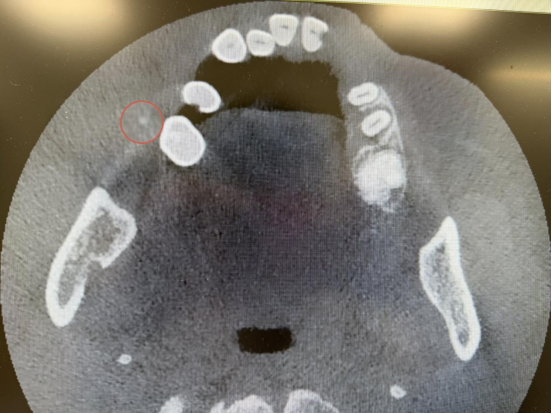

口腔科主任刘超接诊后迅速完善检查,明确诊断为右侧腮腺区导管结石。传统手术需要全身麻醉切除腮腺体,创伤大。考虑到患者年龄较高,且有明确心梗病史,术前检查提示心率过慢,全身麻醉可能诱发心源性意外,手术风险极高,常规方案根本无法实施。

面对该院尚无先例,以及常规手术无法开展的棘手状况,刘超在全面、严谨评估患者情况后,决定采用内镜微创取石术,并大胆选择局部麻醉方案,以最大限度规避心源性风险、减轻患者负担。

在无先例、高风险、强压力的情况下,刘超带领团队凭借深厚的专业功底、丰富的临床经验与精湛的手术操作,成功在内镜下完整取出结石,全程未损伤重要神经血管,顺利完成了这例该院开创性的高难度口腔微创手术。